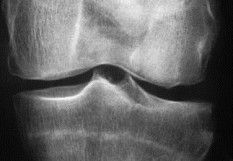

La ministre de la Santé, Agnès Buzyn, vient d’acter la décision de dérembourser tous les traitements à base d’acide hyaluronique injectable dans l’arthrose du genou à partir du 1er décembre 2017. L’Association française de lutte anti-rhumatismale (Aflar) et le Collège français des médecins rhumatologues (CFMR) s’élèvent contre cette décision qui, selon elles, va à l’encontre des récentes études qui attestent de l’efficacité de ces traitements.

Encore une fois, l’Aflar proteste. Encore une fois, l’arsenal thérapeutique de l’arthrose du genou à la disposition des rhumatologues se réduit. Agnès Buzyn vient en effet d’acter la décision de dérembourser tous les traitements à base d’acide hyaluronique injectable dans l’arthrose du genou à partir du 1er décembre 2017. Cette décision prise par le ministère de la Santé va à l’encontre des récentes études qui attestent de l’efficacité de ces traitements. L’Aflar, représentée par son président, le Dr Laurent Grange, et le CFMR, représenté par son président, le Dr Pierre Monod, "s’élèvent contre cette décision et décident de continuer le combat pour qu’elle soit réévaluée". L’Aflar et le CFMR estiment que ce déremboursement "est médicalement et scientifiquement injustifié, médico-économiquement contre-productif, et socialement inéquitable". Ils demandent à la ministre "la remise à plat et le ré-examen serein de ce dossier". Le déremboursement des solutions à base d’acide hyaluronique avait été annoncé à compter du 1er juin 2017 au Journal Officiel du 28 mars 2017. Le service rendu avait été jugé insuffisant par la Commission nationale d’évaluation des dispositifs médicaux et des technologies de santé (CNEDiMTS). Pourtant, de nouveaux arguments scientifiques, portés par plusieurs publications récentes, soulignent l’efficacité et la bonne tolérance de ce traitement par rapport aux autres utilisés dans l’arthrose du genou. Pour l’Aflar et le CFMR, "ces données justifient le maintien d’un remboursement pour un traitement dont l’effet certes modéré, est bien réel et qui reste celui qui offre le meilleur rapport bénéfice-risque parmi les différentes options pharmacologiques dans cette maladie : supérieur à celui des antalgiques et à celui des anti-inflammatoires". Selon le communiqué de presse du 30 novembre de ces deux sociétés, "ce déremboursement va avoir deux conséquences : d’abord celle de priver les patients les plus défavorisés d’un accès à des soins de qualité, 85 % des patients avec un revenu inférieur à 1 000 € rencontrent des problèmes d'accès aux soins dans l'arthrose (Claude Le Pen, Revue du Rhumatisme,  72 (2005) 1326-1330) ; Ensuite celle de reporter les prescriptions vers des traitements plus iatrogènes, plus coûteux pour l’assurance maladie et pas plus efficaces et accélérer le recours des patients à la chirurgie prothétique, qui n’est pas toujours la panacée, qui est très coûteuse, et non dénuée de dangers. Opérer plus tôt, plus jeune, risque d’être lourd de conséquence dans un avenir proche". Une pétition a récolté à ce jour près de 383 000 signatures pour dire "non" à ce  déremboursement. L’Aflar "déplore de ne pas avoir été entendu alors qu’aucune pétition n’a à ce jour rassemblé autant de patients".